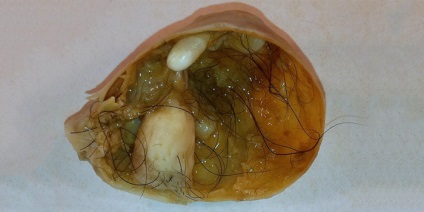

chisturi dermoid (toamele)

Acestea sunt tumori benigne ale straturilor germinale in curs de dezvoltare 2-3, aproape toate dintre ele conțin o componentă a țesutului adipos. Apar, de obicei asimptomatice, sunt detectate accidental in timpul ultrasunete. RMN-ul este utilizat pentru diagnosticul diferențial al chisturilor endometrial. Când Teratoamele T1 au un mod de intensitate mică, contururi indistinct, iar modul de intensitate a semnalului T2 este mare.

chist ovarian dermoid